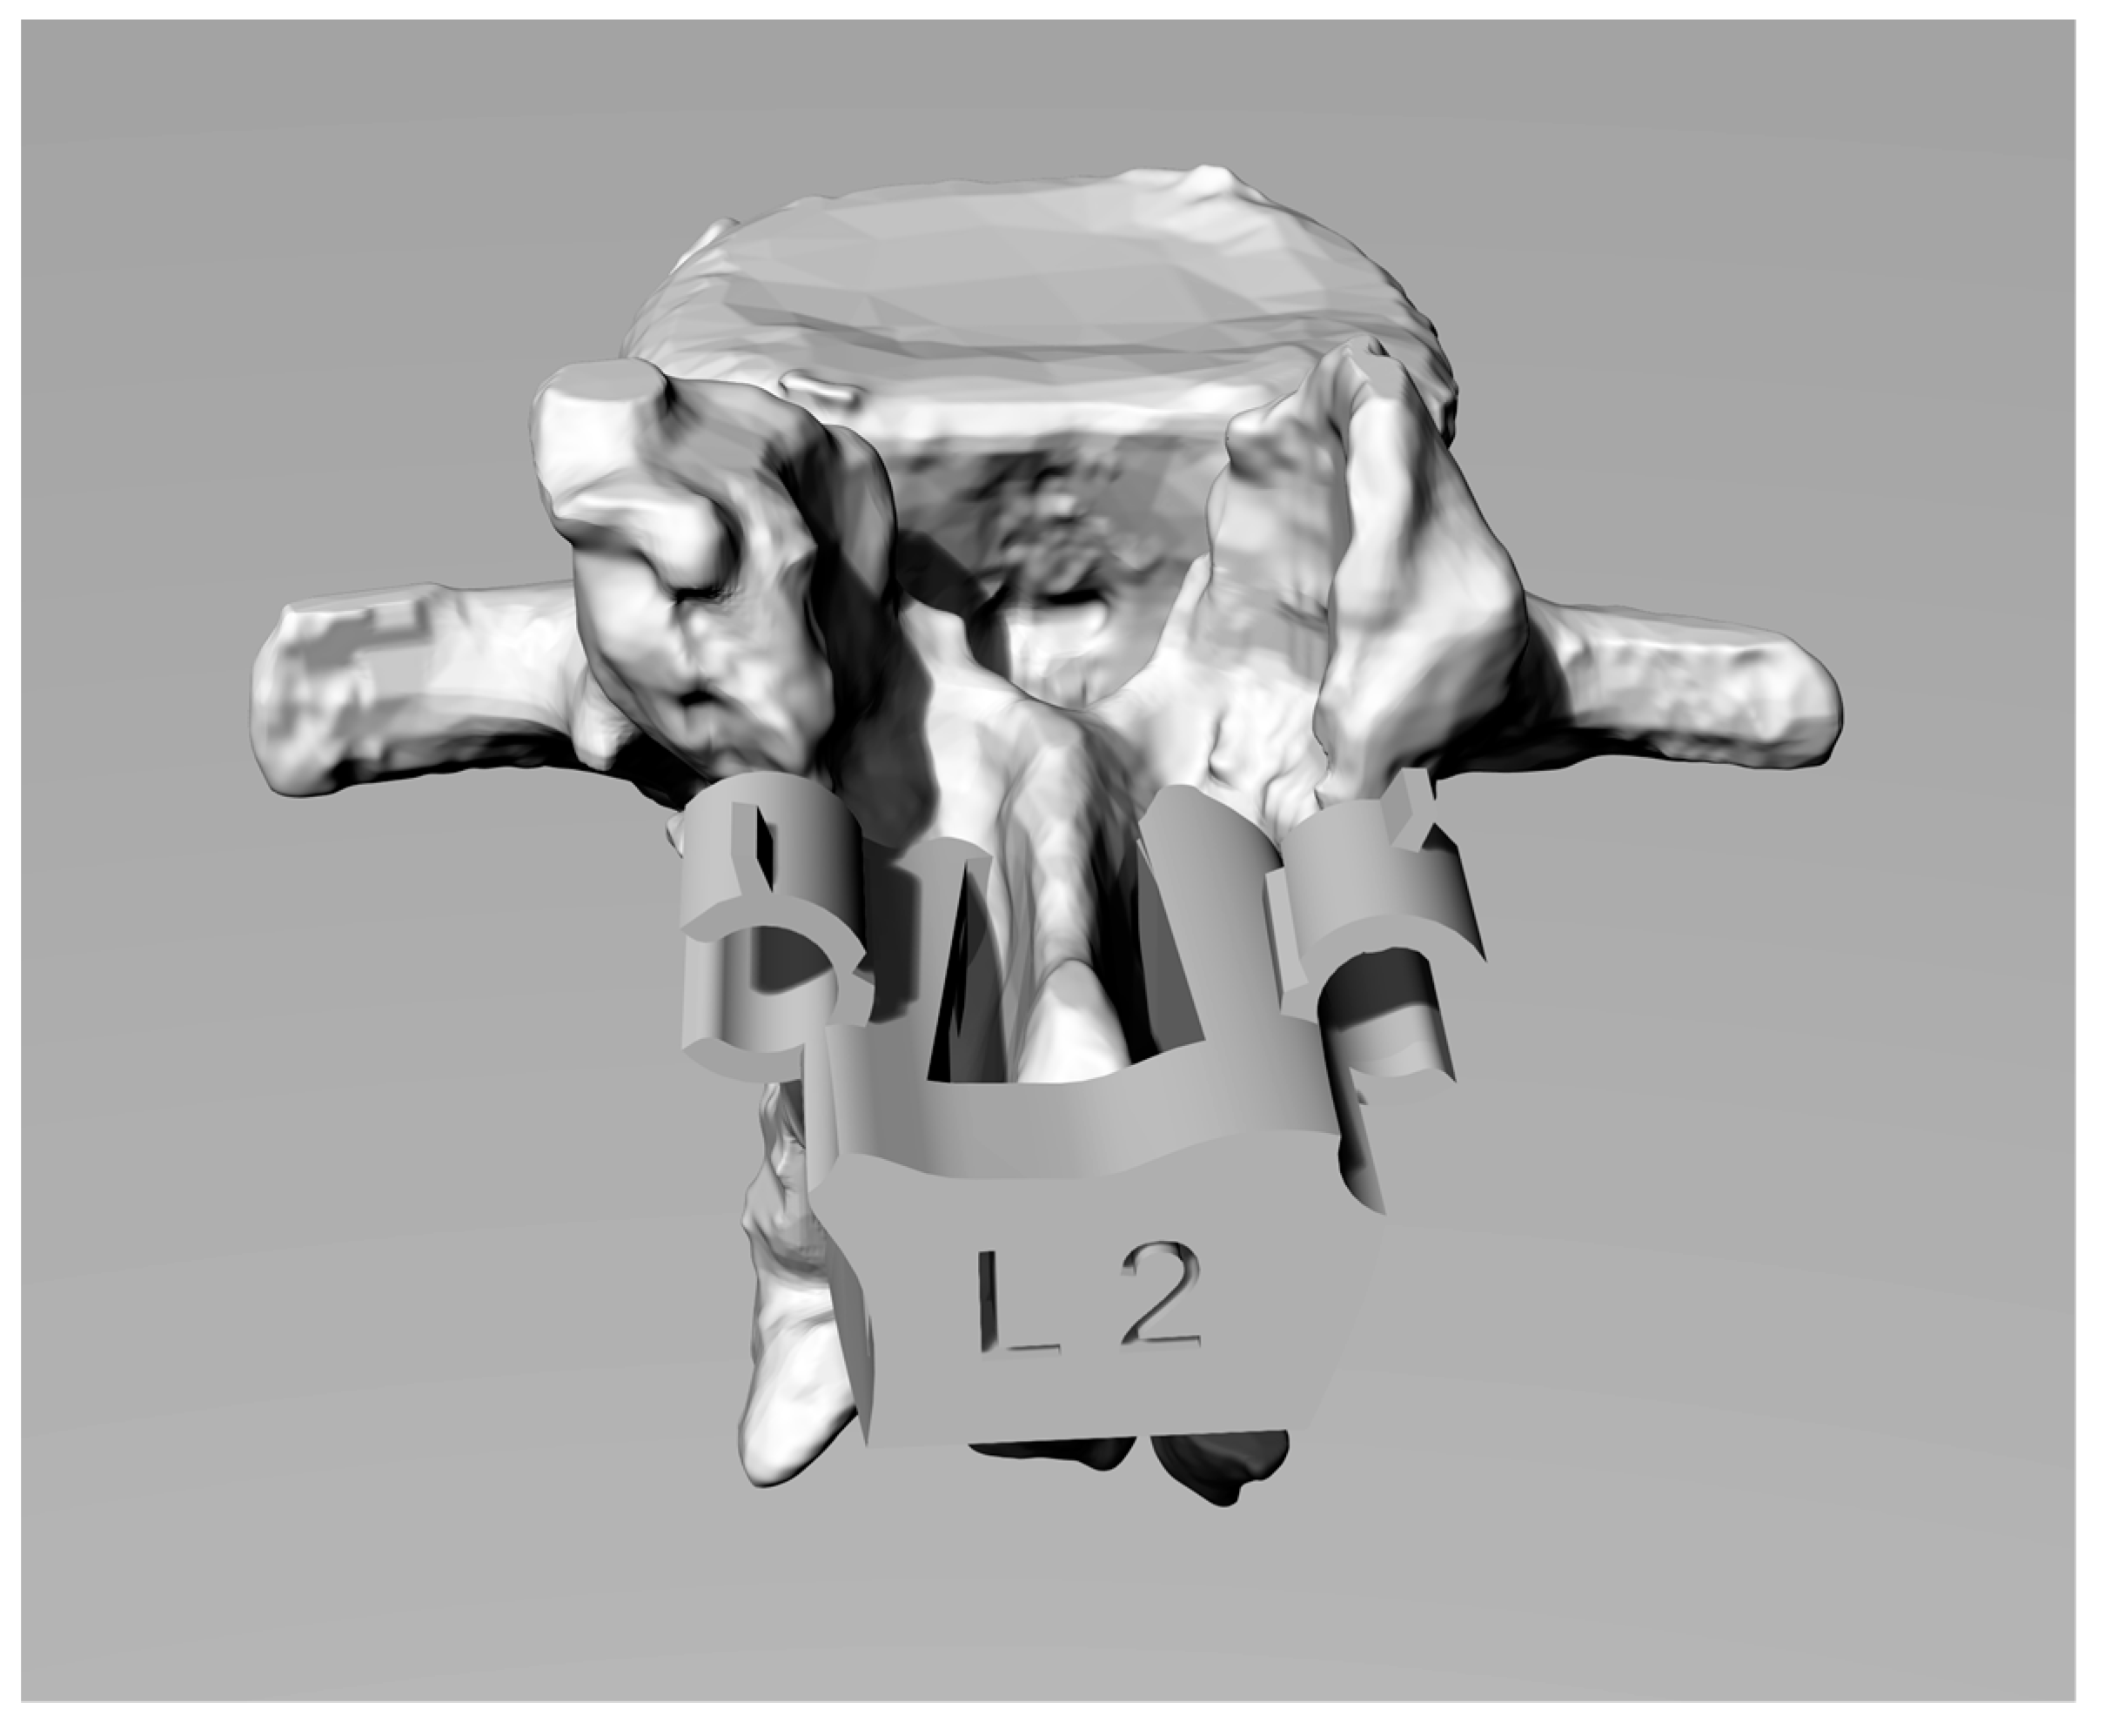

Therefore, it is appropriate to cut the 3D model of the template in its internal surfaces so as not to generate interference and under-cuts with the surfaces of the spinous process. On the solid, tubes and holes have to be created along the already verified trajectories for creating the guides for the screws. Figure 2 shows the final shape of the solid.

2.6. Innovative Engaging and Disengaging Device

The surgical operation of “skeletonization” (removing all the soft tissue attached to the bone structure of the vertebra) may generate small scraps of tissue or bone due to an imperfect cut during the skeletonization. To avoid matching problems between the vertebra and the template and to simplify the engagement and positioning of the template itself on the exposed surfaces of the vertebra, some tube structures have been generated on the interface surface of the template (see Figure 3). It has been verified that very small residual tissues or bone are about half a millimetre in diameter for two reasons: the precision capacity of the prototyping machine, and the hypothesis that any pieces of “waste” tissue larger than this size can be easily identified and removed by hand.

The holes are through-holes where the geometry of the mask allows it and are arranged randomly on the surface (it would have been impossible to define a systematic criterion given that the surfaces are all extremely different from each other) to fit in the free space among the tubes and avoid generating interference in the coupling between the surfaces of the template and those of the vertebral lamina.

In in vivo testing, a pre-notched tube (see Figure 4) used as Kirschner/screw guide on the template has been designed for simplifying the template disengagement once a screw is inserted. After the insertion of the screw, the surgeon can easily break the pre-notched tube without creating plastic scraps, using the small flat spline on the tube [16].

Figure 2. 3D model of template.

Figure 3. 3D model of template with innovative engage system.

Figure 4. Customized template positioned on the L2 vertebra surface with notched tubes and tongues.